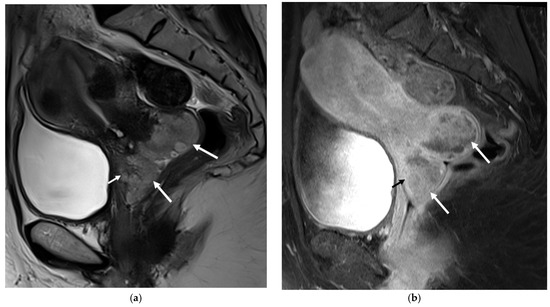

Angioleiomyoma, a rare variant of leiomyoma, is a benign tumor of mesenchymal origin. Angioleiomyomas of the female urogenital tract are extremely rare, with only six cases of uterine cervical angioleiomyoma previously reported in the literature. In this case study, we report on a [...] Read more.

Angioleiomyoma, a rare variant of leiomyoma, is a benign tumor of mesenchymal origin. Angioleiomyomas of the female urogenital tract are extremely rare, with only six cases of uterine cervical angioleiomyoma previously reported in the literature. In this case study, we report on a 49-year-old female patient who presented with menorrhagia whose initial magnetic resonance imaging (MRI) findings suggested cervical squamous cell carcinoma (SCC). However, following the hysterectomy, histological examination confirmed the lesion to be angioleiomyoma. To the best of our knowledge, there have been no previously reported cases of angioleiomyomas presenting with MRI findings that are suggestive of uterine SCC. Recognizing that angioleiomyomas can mimic uterine malignancies on MRI may prove beneficial for future diagnostic and treatment strategies. Full article